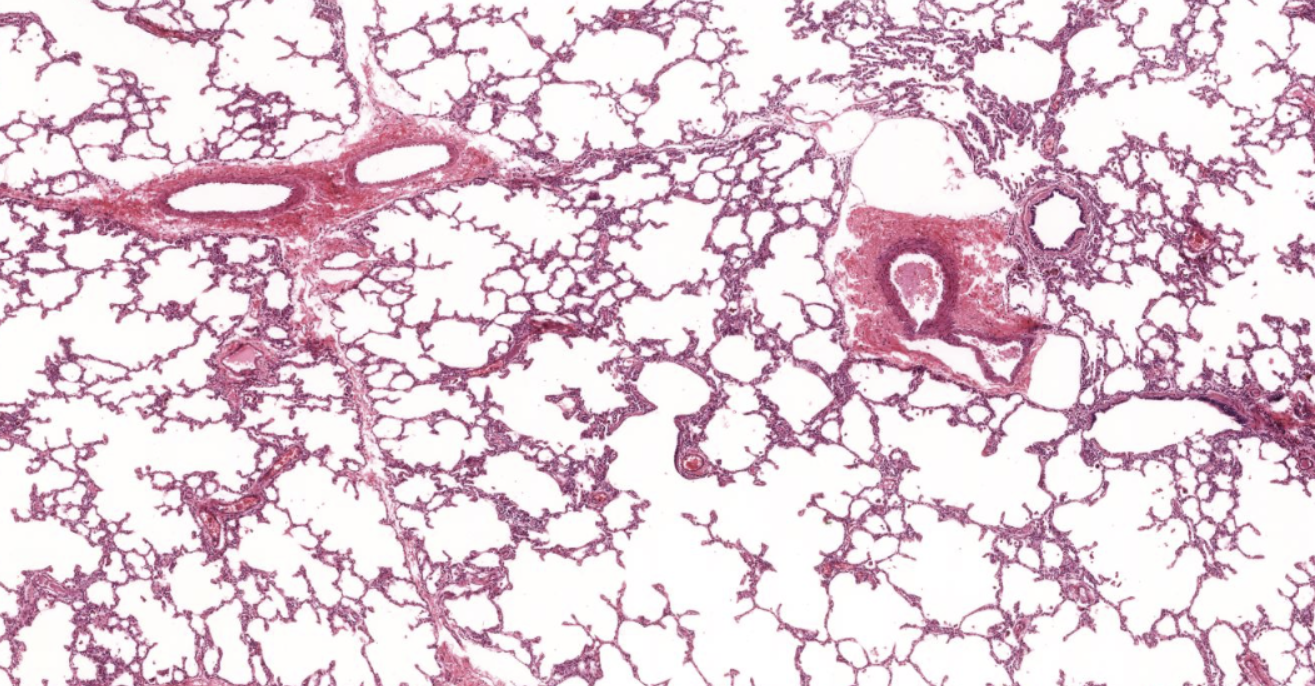

Lung tissue

NOTICE: THE OPEN SPACE OF THE ALVEOLI